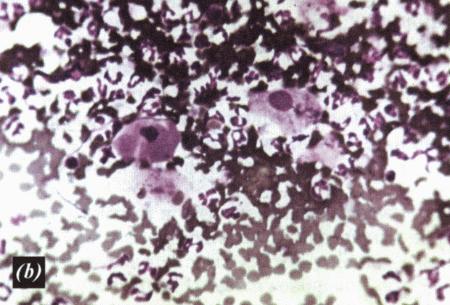

Фиг. 2.2.

Вагинальные выделения кошки (а). Выделения, типичные для фазы эструса. Большая часть клеток представляет собой безъядерные кератинизированные клетки или клетки с пикнотическим ядром. Присутствуют промежуточные клетки (b). Выделения, характерные для метэструса, — «течки», иногда наблюдаемой у кошек в конце эструса. Присутствуют поверхностные и промежуточные клетки, повышено содержание лейкоцитов. Этот короткий метэструс наблюдается в течение 24–48 часов (см. Приложение)